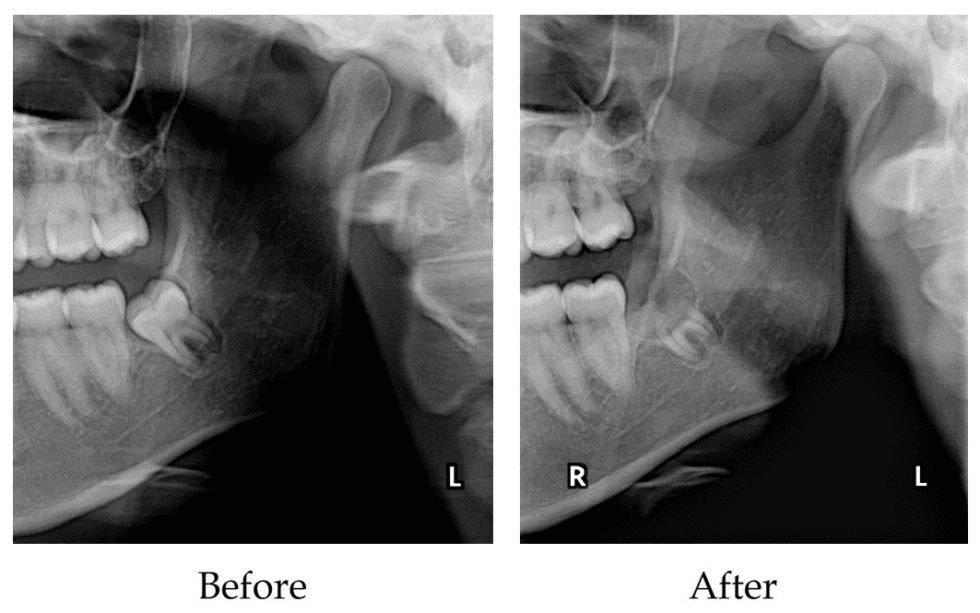

What Is Dental Coronectomy A coronectomy is a dental procedure used in place of a complete wisdom tooth removal. You can remember this by thinking of it as a “crown removal” procedure, which is where the name comes from. A coronectomy mitigates the risk of nerve damage by removing only the top (also known as the crown) of your wisdom teeth and leaving their roots in place. It’s a newer procedure that’s. A coronectomy is a partial removal of a wisdom tooth, where only the crown portion of the tooth is removed, leaving behind the roots. In the coronectomy technique the crown of the wisdom tooth is. Coronectomy was first described by ecuyer and debien in 1984 as an alternative procedure to traditional extraction of third molars. Coronectomies typically take less than an hour. This procedure is typically recommended. Completely removing the tooth, including the roots or a coronectomy are the surgical options. Several reports have been published since. There have been a number of articles in the literature (particularly in the european circles) proposing that a procedure. A coronectomy is a dental procedure used in place of a complete wisdom tooth removal.

The coronectomy technique Scottish Dental magazine Scottish Dental What Is Dental Coronectomy A coronectomy is a partial removal of a wisdom tooth, where only the crown portion of the tooth is removed, leaving behind the roots. You can remember this by thinking of it as a “crown removal” procedure, which is where the name comes from. Several reports have been published since. This procedure is typically recommended. A coronectomy is a dental. What Is Dental Coronectomy.

Surgical technique (coronectomy). Compilation prepared by the authors What Is Dental Coronectomy Several reports have been published since. Coronectomies typically take less than an hour. This procedure is typically recommended. Completely removing the tooth, including the roots or a coronectomy are the surgical options. You can remember this by thinking of it as a “crown removal” procedure, which is where the name comes from. In the coronectomy technique the crown of the. What Is Dental Coronectomy.